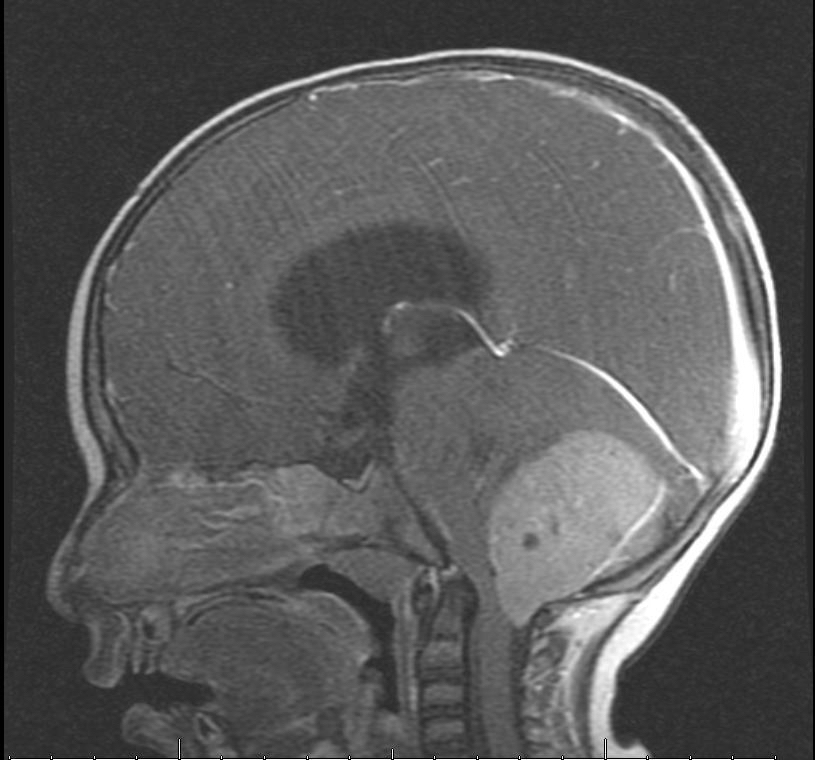

وأضافت: على الفور تم إجراء الفحص السريري والمخبري وأشعة مقطعية للرأس، والرنين المغناطيسي الذي بين وجود ورم كبير على شكل كتلة في منطقة المخيخ وتسببت له بضغط شديد على المراكز الحيوية في جذع الدماغ وأيضًا استسقاء دماغي شديد.

وبيّن الفريق الطبي المعالج للحالة أنه تقرر على الفور إجراء تدخل جراحي نادر ومعقد، نظرًا لصعوبة مكان الورم، حيث تم استئصاله بشكل كامل دون أي أعرض أو مضاعفات على دماغ الطفل.

وأكد إجراء أشعة الرنين المغناطيسي لمنطقة الرأس مرة أخرى للتأكد من خلوه من أي بقايا لكتل ورمية، وبينت الأشعة سلامة المنطقة.